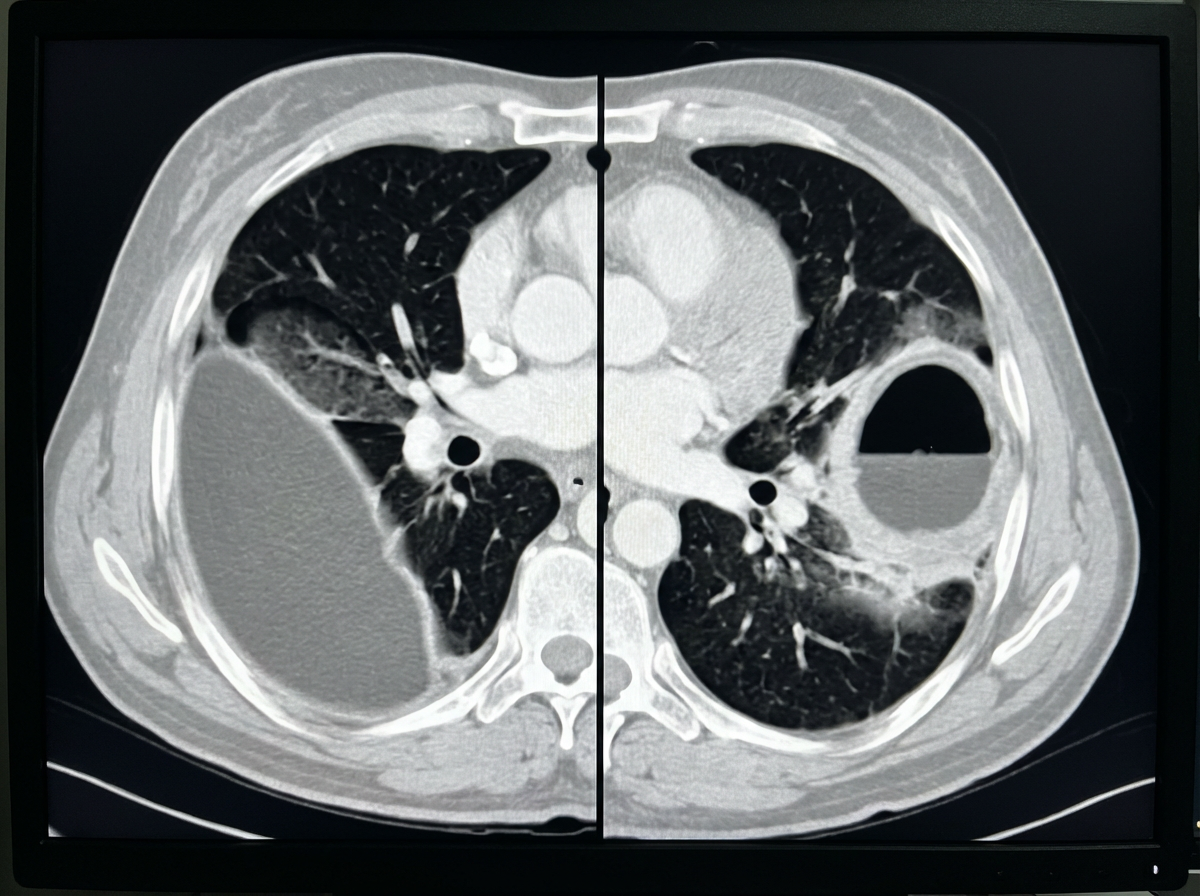

Chest CT is the clearest test. On CT, an empyema is a lens‑shaped pleural collection that compresses the lung. The split pleura sign (both pleural layers enhancing around the fluid) supports empyema. A lung abscess is a thick‑walled cavity inside lung tissue, typically with a visible air–fluid level and sharp angles where it meets the pleura.

Key point: CT shows whether pus is around the lung or inside the lung, and that difference guides treatment.